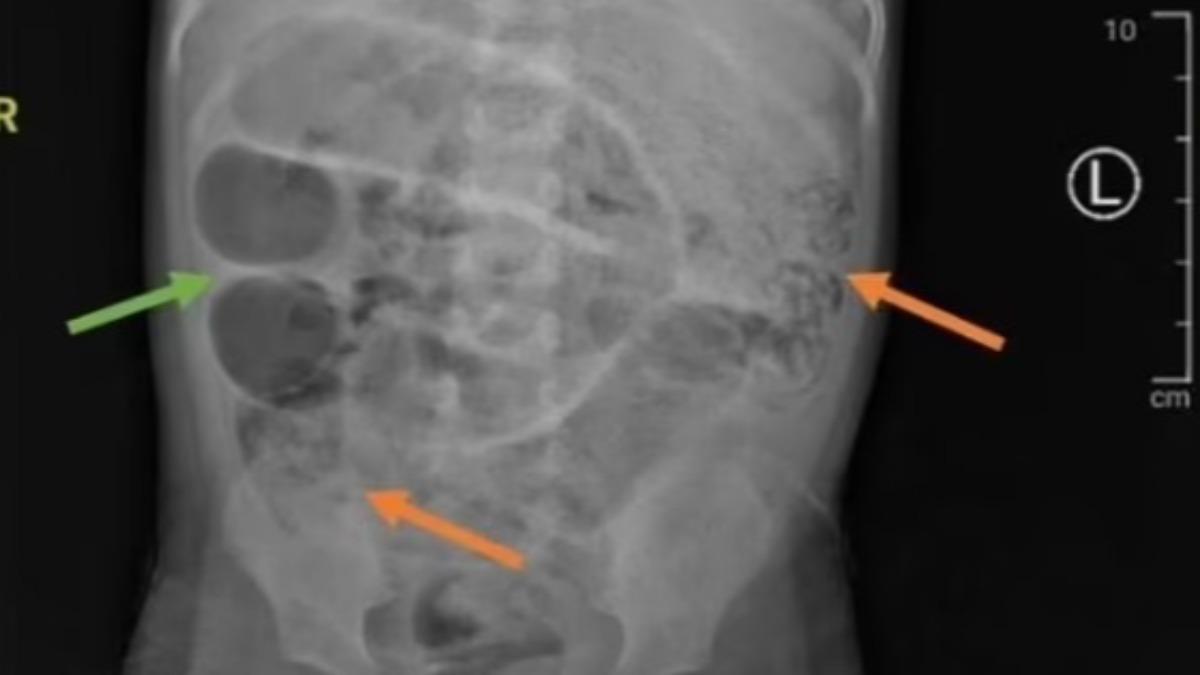

綜合報道,這名3歲男童腹部嚴重腹脹、發燒且3天無法排便,他的父母出於擔心便就醫求助,起初院方診斷這只是單純便秘,但隔天男童開始嘔出蠕蟲,X光顯示胃部出現不明灰色腫塊;血液檢查亦顯示男孩患有貧血,相信是由於身體無法產生足夠的健康紅血球而發生,亦是感染寄生蟲的常見警訊,因為有些蛔蟲以腸道中的血液為食物、進而導致慢性失血和鐵含量降低。